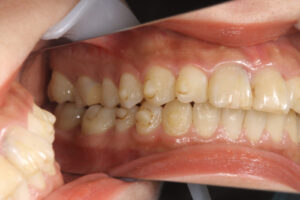

初診時に前歯が噛んでいない

インビザラインで失敗した23歳女性

初診時に奥歯が噛んでいない

ワイヤー矯正で全体の歯が噛んでいる